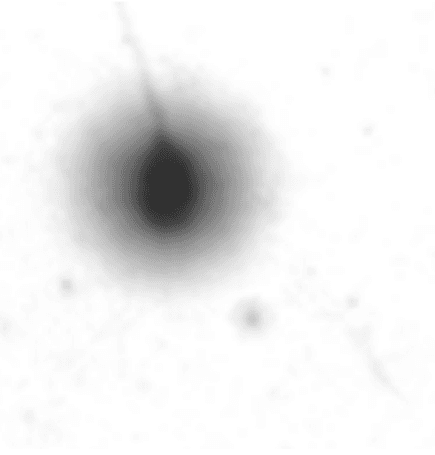

W naszym laboratorium badanie integralności chromatyny wykonywane jest metodą SCD (ang. Sperm Chromatin Dispersion). Test oparty jest na reakcji denaturacji kwasowej DNA. Podczas inkubacji ze specjalistycznymi odczynnikami w próbkach zawierających prawidłowe DNA dochodzi do rozplecenia oraz wybarwienia dwuniciowej struktury kwasu nukleinowego na skutek zerwania wiązań łączących nici DNA ze sobą, a w obrazie mikroskopowym zauważalny jest tzw. efekt halo. U plemników zawierających nieprawidłową strukturę chromatyny efekt halo jest niezauważalny bądź znikomy. Im mniejsze halo obserwujemy pod mikroskopem, tym stopień fragmentacji chromatyny jest wyższy.

1. Obraz mikroskopowy plemnika z wyraźnym halo - chromatyna niepofragmenowana.

2. Obraz mikroskopowy plemnika, brak halo – chromatyna pofragmenowana.

3. Porównanie plemników z odmienną strukturą chromatyny - plemnik górny z prawidłową chromatyną, plemnik dolny bez efektu halo - chromatyna pofragmentowana.